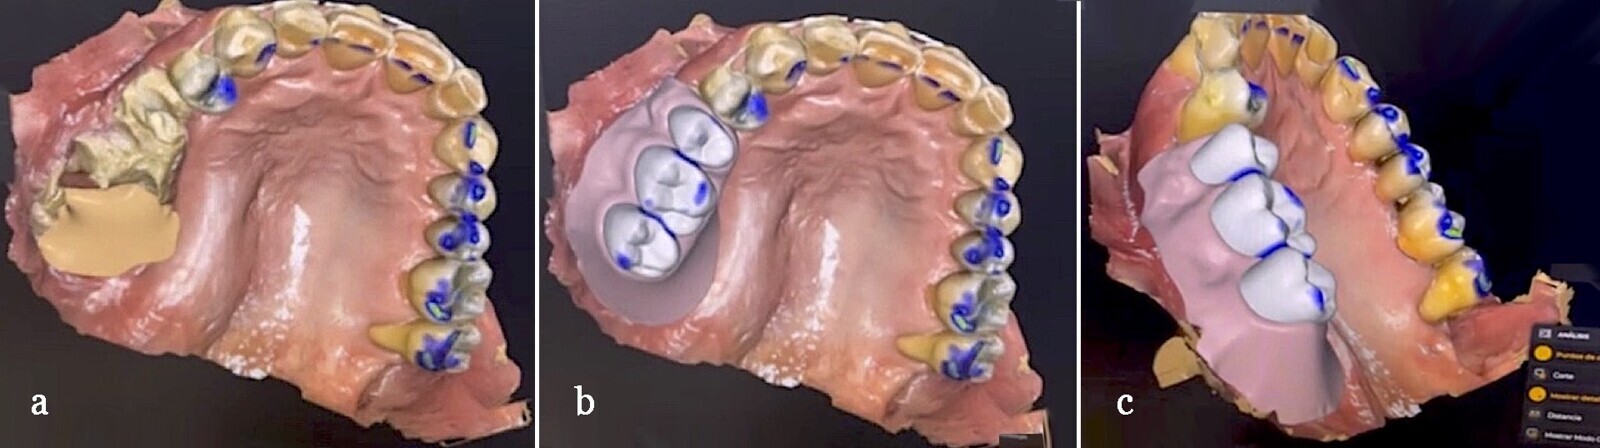

Primeramente, se realiza toma de impresiones en alginato para obtener modelos preliminares. Sin embargo, las impresiones definitivas fueron tomadas con un escáner intraoral, que fue el manejo ideal en este caso ya que nos brindó las medidas exactas sin problemas de expansión por mal manejo de material.

Figura 4. Imágenes de la toma de impresión con escáner intraoral y diseño mediante sistema CAD/CAM para la rehabilitación oral del caso (a), en las que se observa una amplia exposición ósea sin adecuada cicatrización (b).

Figura 5. Vistas desde diferentes ángulos obtenidas de la planificación digital del caso con un sistema CAM.